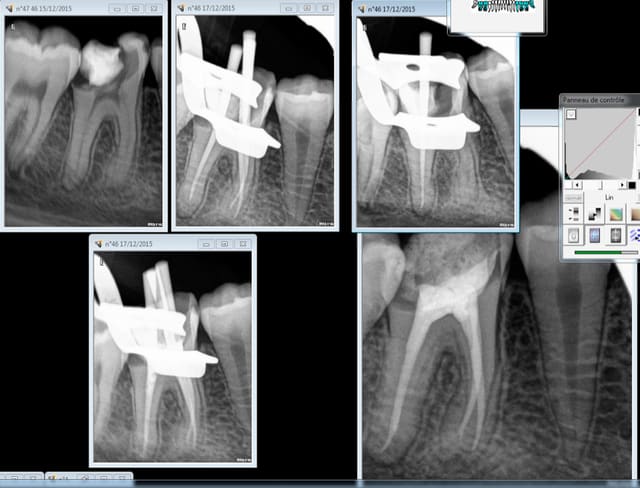

17/12/2015 à 12h10

Bon là ca s'est barré à la fin. -)))))

Endo moyenne.

Capture d e cran 2015 12 17 11.04 - Eugenol

Capture d e cran 2015 12 17 11.07 - Eugenol